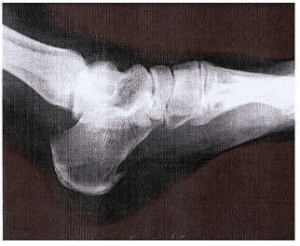

痛み止めが効きません 踵骨棘

足は痛くなって整形外科へ行ったが、レントゲン、MRIどれで検査しても異常ないと言われたが、痛い 仕方なく別の整形外科へと回ったが5か所に行ってもどこも同じような結果 しかし現実に痛くてたまらなく、東京の足の […]